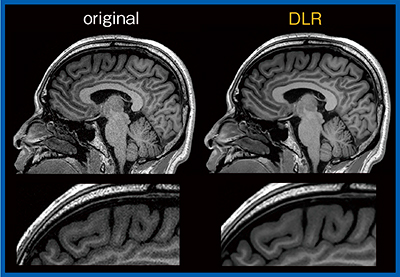

近年,高分解能3D-T1強調画像から脳皮質の厚さや体積を測定し,認知症や精神疾患の評価を行う研究手法が多く見られる。このような画像解析では,画像分解能が高く,かつノイズの少ない画像を用いることにより,測定精度が高くなると考えられる。7T MRIでスライス厚1mmと0.5mmを比較したところ,0.5mmではパーシャルボリューム効果の影響が低減し,皮質の厚さが1/3〜1/6になるという報告もある2)。今回,0.8mm iso voxelのMPRAGE画像(図5)を用いて検討したところ,オリジナル画像と比較してDLR画像では前頭葉の画像解析エラーが低減した。このように,DLRは定量解析研究にも寄与すると思われる。

図5 0.8mm iso voxel MPRAGE画像におけるノイズの低減